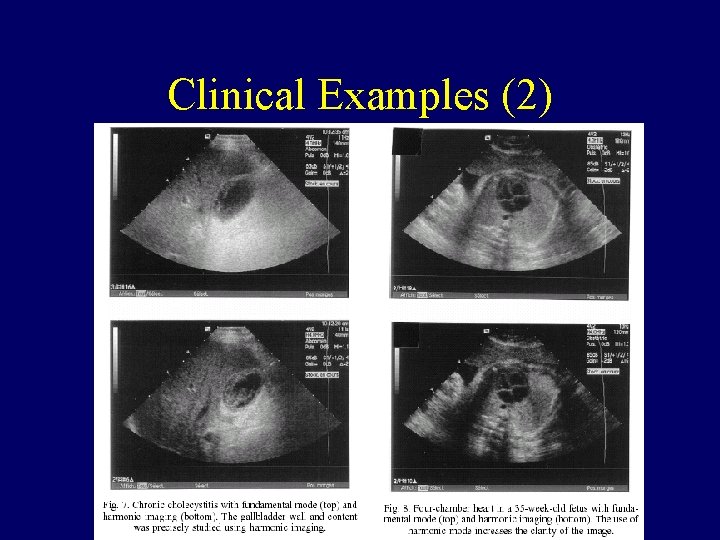

Clinical Examples (2)